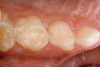

Figure 12  Final view showing treated surface of mesial of tooth A.

Figure 12

Specially designed dental wedges are inserted to slightly separate the carious tooth from adjacent teeth. A 15% hydrochloric gel is used to remove the "pseudointact" surface and open the pore system of the incipient lesion body (Figure 7).85 After rinsing (Figure 8), the area is dried with ethanol (Figure 9), followed by dry air. Then, the infiltrant is applied and allowed to penetrate the lesion pores by capillary action for 3 minutes (Figure 10). Any excess material is removed with dental floss, and the infiltrant is light cured from three angles for 40 seconds (Figure 11). A second layer of infiltrant is applied for 1 minute, and light cured for 40 seconds (Figure 12).86 It should be noted that the infiltrant is not radiopaque because fillers would affect the viscosity. Efficacy of the treatment can be tracked at future visits by lack of lesion progression.